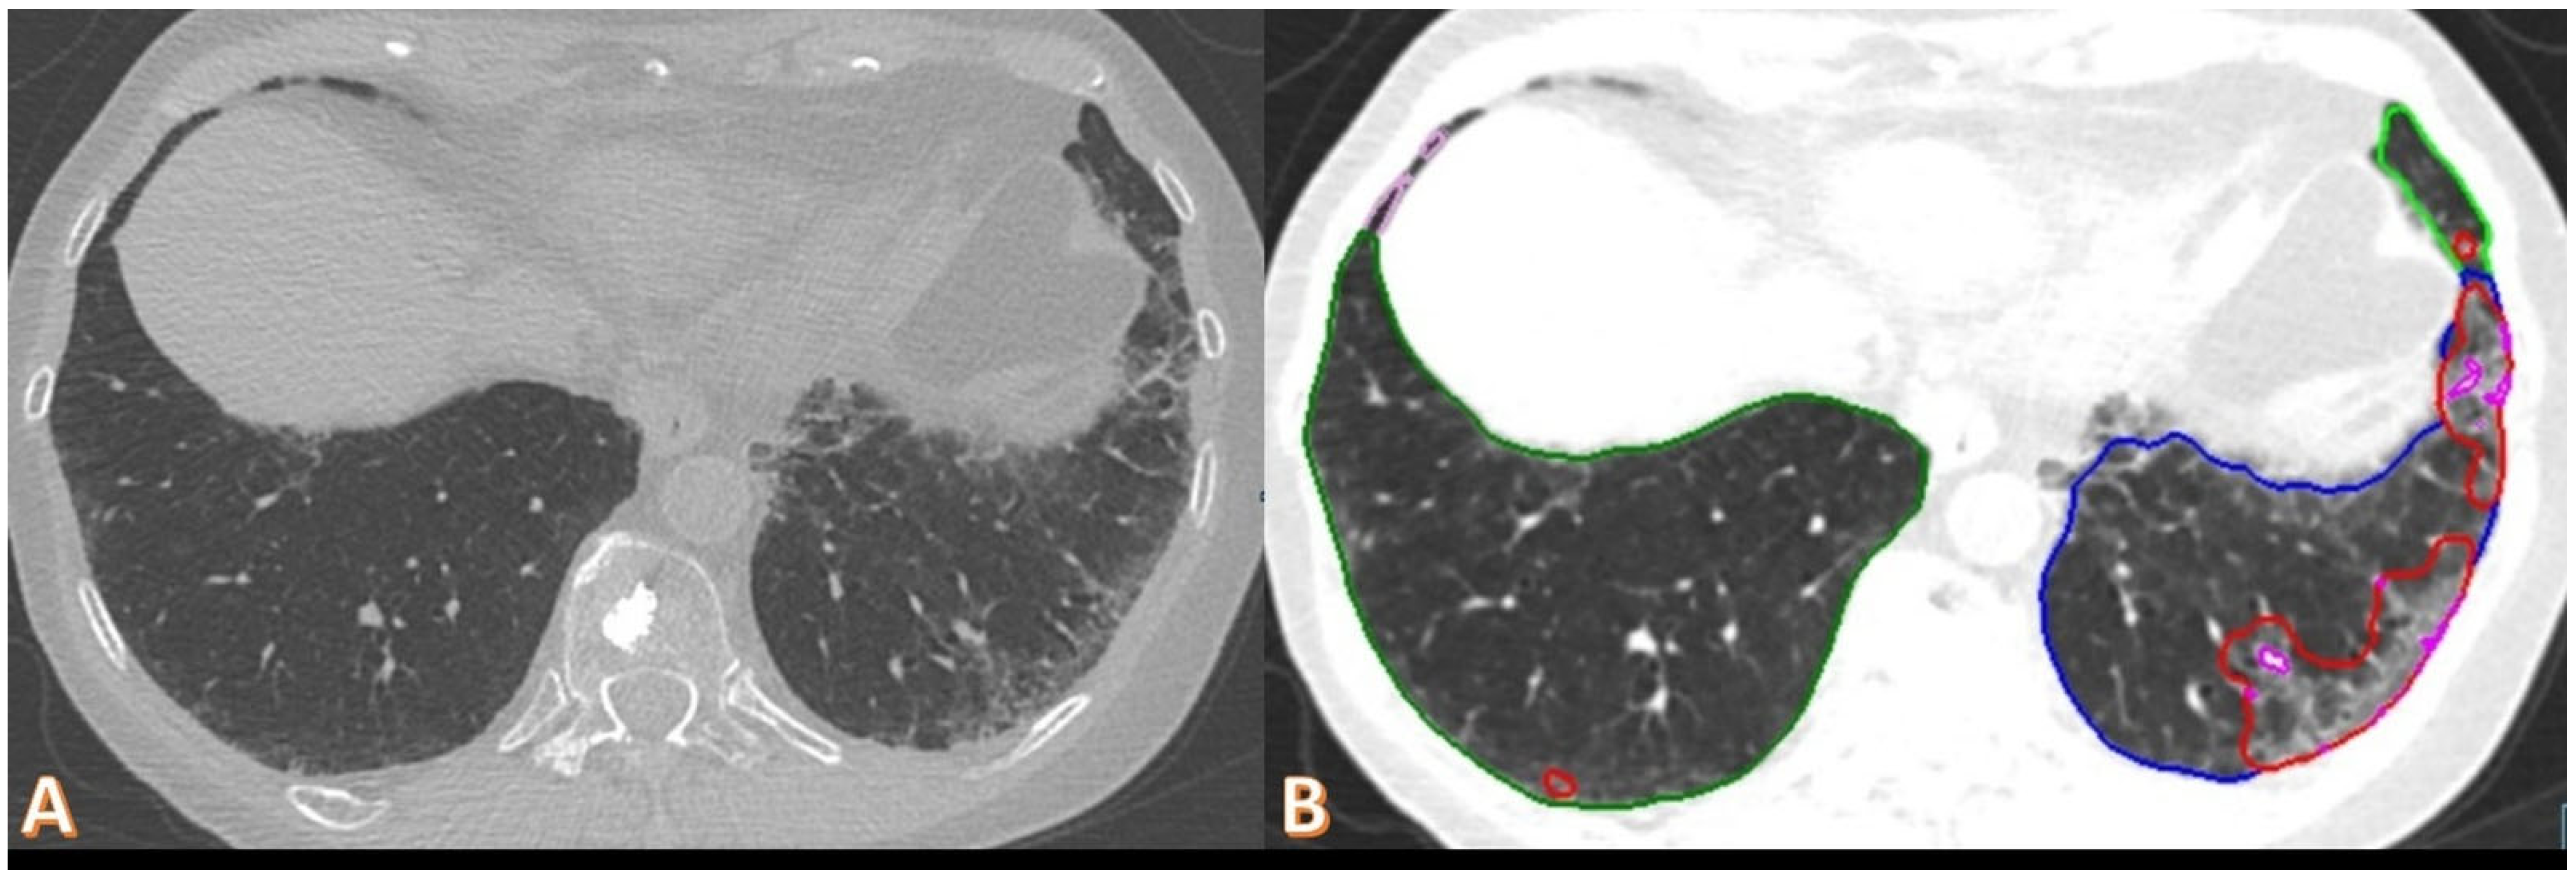

3.3. CT Markers of Lung Function Impairment